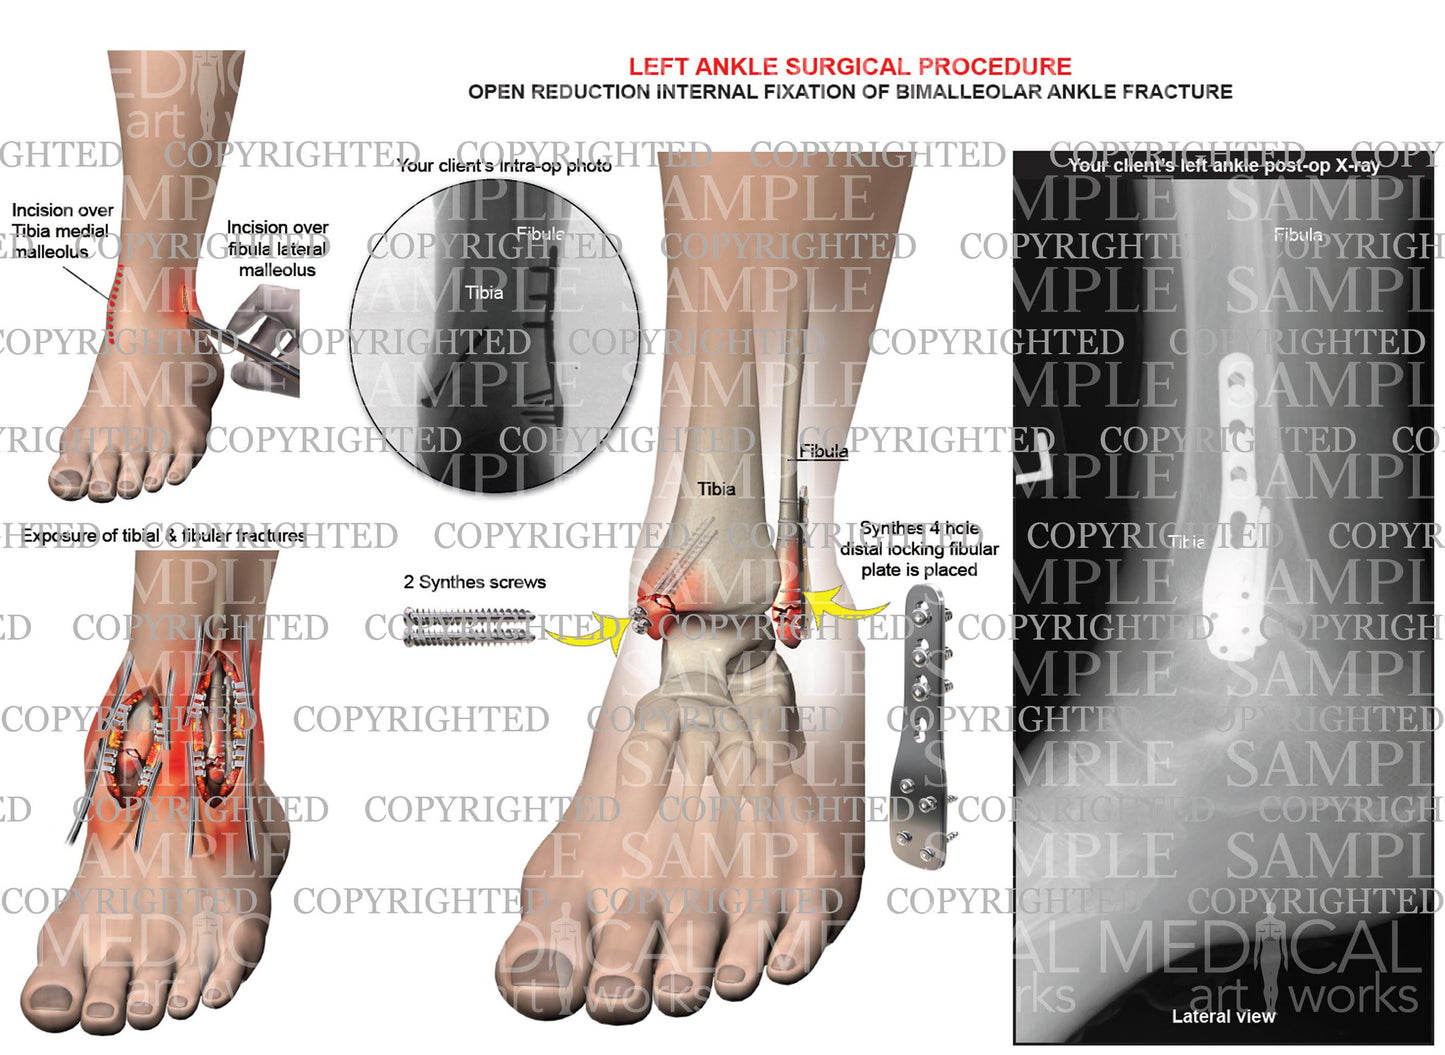

Left ankle and tibia bimalleolar fracture -ORIF

Left ankle and tibia bimalleolar fracture -ORIF

Open reduction internal fixation of bimalleolar ankle fracture. Synthes 4 hole distal locking fibular plate is placed, 2 Synthes screws. Add you own client's post-op x-ray.